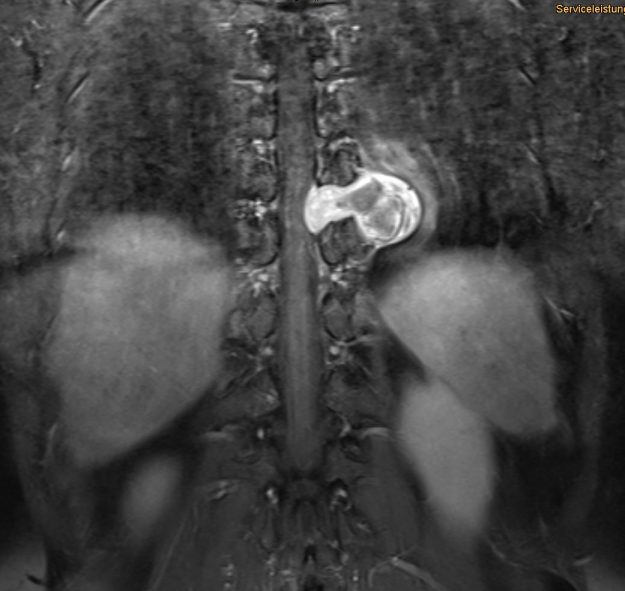

Μετάσταση 10ου Θωρακικού Σπονδύλου (Θ10)

Ασθενής άνδρας 72 ετών με έντονη ραχιαλγία και ιστορικό καρκίνου του πνεύμονα. Ο απεικονιστικός έλεγχος με μαγνητική και αξονική τομογραφία της σπονδυλικής στήλης ανέδειξε μάζα κυρίως στο σώμα του 10ου θωρακικού σπονδύλου (Θ10) με περιβρογχισμό και πίεση επί του νωτιαίου μυελού. (Σημειώστε και τη διήθηση του Θ9 σπονδύλου, χωρίς οστεόλυση). Διενεργήθη αποσυμπίεση του νωτιαίου μυελού…